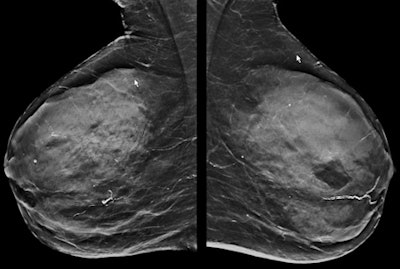

The dense mammogram (top) is negative, but an abbreviated breast MRI study (below) in the same patient is positive for small invasive cancer. In the first postcontrast subtracted image (Fast; bottom) of the slice and the corresponding maximum intensity projection image, the cancer can be clearly seen in the same patient. The patient underwent a MRI-guided biopsy, which confirmed presence of a grade 2 invasive cancer (no special type), 8 mm in longest diameter. All images courtesy of Dr. Christiane Kuhl."Of those patients who have breast-conserving surgery, about 14% have more extensive surgery due to MRI but 12% to 13% have less extensive surgery," Sardanelli noted. "The reoperation rate is lower in those patients who had an MRI, but this has to be read in the light of the higher rate of mastectomies."

In particular, certain kinds of lesions are associated with an increased risk of breast cancer. Atypical ductal hyperplasia is associated with a 40% increased risk of breast cancer, and lobular intraepithelial neoplasia and flat epithelial atypia are both associated with a 21% increased risk. These lesions are treated with intensified surveillance and possibly tamoxifen, so while they may be called false positives on MRI, they are not completely harmless, even though they are still categorized as benign, added Kuhl, who is a keen advocate of abbreviated breast MRI studies (see images above).